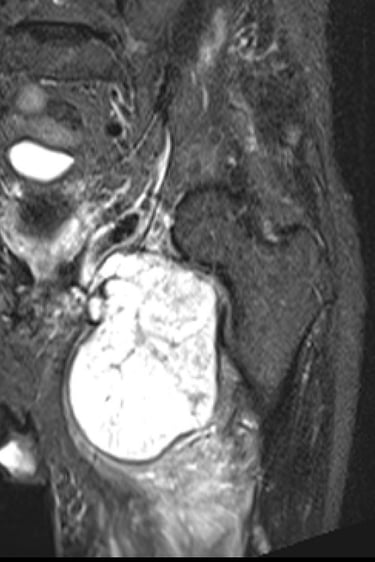

This is the second most common type of primary bone cancer, particularly over the age of 40. It often develops from normal cartilage cells or may occur in patients with pre-existing benign cartilage tumours eg. enchondromas, multiple osteochondromas, Ollier or Maffucci syndrome. Most occur in the femur, humerus, pelvis and around the knee but can occur in any bone. Most patients are treated with surgery alone as these are generally not responsive to chemotherapy or radiotherapy.

Diagnosis of chondrosarcoma can be very challenging. These can range from low grade (grade1) to high grade (dedifferentiated) and diagnosis often require a number of tests. Biopsies are often not recommended as these tumours are difficult to differentiate histologically. Diagnosis is generally made clinically and radiologically.